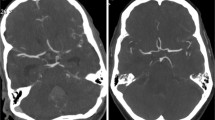

The study population included consecutive adult patients who presented with acute neurologic symptoms and received a diagnostic UHR-CTA or NR-CTA at our department from September 2021 to December 2022. Exclusion criteria were distinct motion artifacts, beam-hardening artifacts and an insufficient contrast due to venous overlay (Fig. 1).

We identified 177 patients to be eligible for inclusion in the study but 20 patients were excluded due to severe artifacts (movement or beam hardening), insufficient contrast or due to venous contamination, leading to a final study cohort of n = 155 (M = 64; F = 91; age = 67.2 ± 11.3 years). The two sub-cohorts consisted of NR-CT: n = 73 (F = 49; M = 24) and UHR-CT n = 82 (F = 42; M = 40). Of the patients in the NR-CTA data set 12 were excluded (3 patients = severe metal artifacts; 1 patient = severe motion artifact and 8 patients = insufficient arterial contrast) and 8 patients of the UHR-CTA data set were excluded (7 patients due to insufficient arterial contrast and 1 patient due to metal artifacts).

In comparison to NR-CTA, UHR-CTA showed significantly superior overall image quality. Briefly, UHR-CTA revealed higher image quality (p < 0.001), lower subjective image noise (p < 0.001), less artifacts (p < 0.001), higher overall contrast (p < 0.001) and higher diagnostic confidence (p < 0.001). Dedicated vessel evaluation showed superior neurovascular delineation and visualization of all vessel segments from proximal to distal for UHR-CTA compared to NR-CTA (PICA: UHR-CTA = 4 (3–4) vs NR-CTA = 3 (2–3); P4: UHR-CTA = 4 (3–4) vs NR-CTA = 2 (2–3); M4: UHR-CTA = 4 (4–4) vs NR-CTA = 3 (2–3); A4: UHR-CTA = 4 (3–4) vs NR-CTA = 2 (2–3); all p < 0.001). Medians and frequencies of the subjective assessment are demonstrated in Fig. 3 and Table 3. Interreader agreement between the three readers was good to almost perfect for image quality evaluation (kappa: 0.7, 0.6, 0.7 and 0.7 for artifacts, image noise, overall image quality and overall, respectively) and good for evaluating the delineation of the small, intracerebral arteries (kappa: 0.7).

A clear depiction and delineation of small, peripheral vessels in a patient example is given in Fig. 4, and the remarkable superiority of UHR-CT in the visualization of peripheral and small vessel branches and their delineation is demonstrated in volume rendering (Fig. 5). The improved image quality of the vertebrobasilar area is also substantial: VA: UHR-CTA = 4 (4–4) vs NR-CTA = 3 (3–4) PICA: UHR-CTA = 4 (3–4) vs NR-CTA = 3 (2–3); AICA: UHR-CTA = 4 (3–4) vs NR-CTA = 3 (2–3). The apparent differences in delineation of peripheral cerebral vessels are illustrated in Fig. 5.